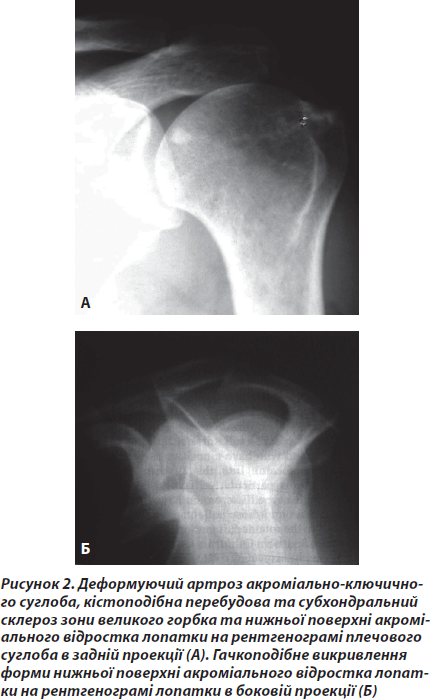

Характерним для хворих було значне зменшення або навіть зникнення болю після введення розчину місцевого анестетика (лідокаїн 2% 10 мл) у субакроміальний простір. Ми назвали цей феномен позитивним тестом субакроміального введення місцевого анестетика. На нашу думку, знеболення в такому випадку свідчить про виявлення locusmorbi, а також виключає прямий зв’язок больового синдрому з шийним відділом хребта. Під час виконання рентгенографії у всіх хворих даної групи виявлялись дегенеративно-дистрофічні зміни акроміально-ключичного суглоба, кістовидна перебудова та/або субхондральний склероз великого горбка та нижньої поверхні акроміального відростка лопатки (рис. 2).

Захворювання даної групи пацієнтів було пов’язане з субакроміальним псевдосуглобом. Він утворений корако-акроміальною дугою (що складається з нижньої поверхні акроміального відростка лопатки, корако-акроміальної зв’язки та задньої поверхні дзьобоподібного відростка лопатки) та частиною епіфіза плечової кістки від місця кріплення малого круглого м’яза до малого горбка з прикріпленням підлопаткового м’яза [10]. Субакроміальну сумку можна вважати своєрідною суглобовою порожниною. Як відомо, елевація плеча забезпечується скороченням дельтоподібного м’яза. Вектори сил, що виникають при її скороченні, направлені в такий спосіб, що зміщують голівку плеча вертикально в напрямку. Одночасне скорочення м’язів РМП притискає голівку до суглобової западини лопатки, протидіючи в такий спосіб зміщувальному зусиллю [10]. Таким чином, у нормі зіткнення між корако-акроміальною дугою та плечовою кісткою з прикріпленими до неї сухожилками не настає. У випадку зниження функції м’язів РМП кожна елевація кінцівки супроводжується більш чи менш сильним стисненням між указаними структурами. Виникає синдром субакроміального зіткнення або стиснення. Причинами гіпофункції м’язів РМП можуть бути перевантаження, пошкодження, а також корінцевий синдром при остеохондрозі шийного відділу хребта. Крайові кісткові розростання нижньої поверхні акроміального відростка лопатки, суглобових кінців акроміально-ключичного суглоба, викривлення форми акроміального виростка лопатки (ІІ–ІІІ морфологічні типи акроміального виростка за Bighliani [9]) обумовлюють звуження субакроміального простору та збільшують вірогідність виникнення синдрому субакроміального конфлікту. Лікування хворих даної групи включало в себе режим безболісних навантажень, лікувальну фізкультуру з укріплення м’язів РМП [2]. За наявності ультразвукових ознак хронічного субакроміального бурситу проводилось однократне внутрішньосуглобове введення 1 мл дипроспану з розчином місцевого анестетика під ультразвуковим контролем. Показаннями до операції вважали відсутність ефекту від адекватного консервативного лікування протягом 2 місяців за наявності крайових кісткових розростань акроміального відростка лопатки, суглобових кінців акроміально-ключичного суглоба, ІІ чи ІІІ морфологічного типу акроміального відростка лопатки за Bighliani. Таким хворим проводили операцію субакроміальної декомпресії під артроскопічним контролем, що включала субакроміальну бурсектомію та резекцію кісткових розростань. У післяопераційному періоді проводилась реабілітація за планом консервативного лікування, наведеним вище. У хворих даної групи досягнуто середнього покращення кількісних показників за шкалою обстеження функції плеча від передопераційних 63,4 до 89,7 % через 18 місяців після операції.